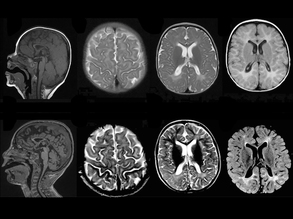

Brain Box